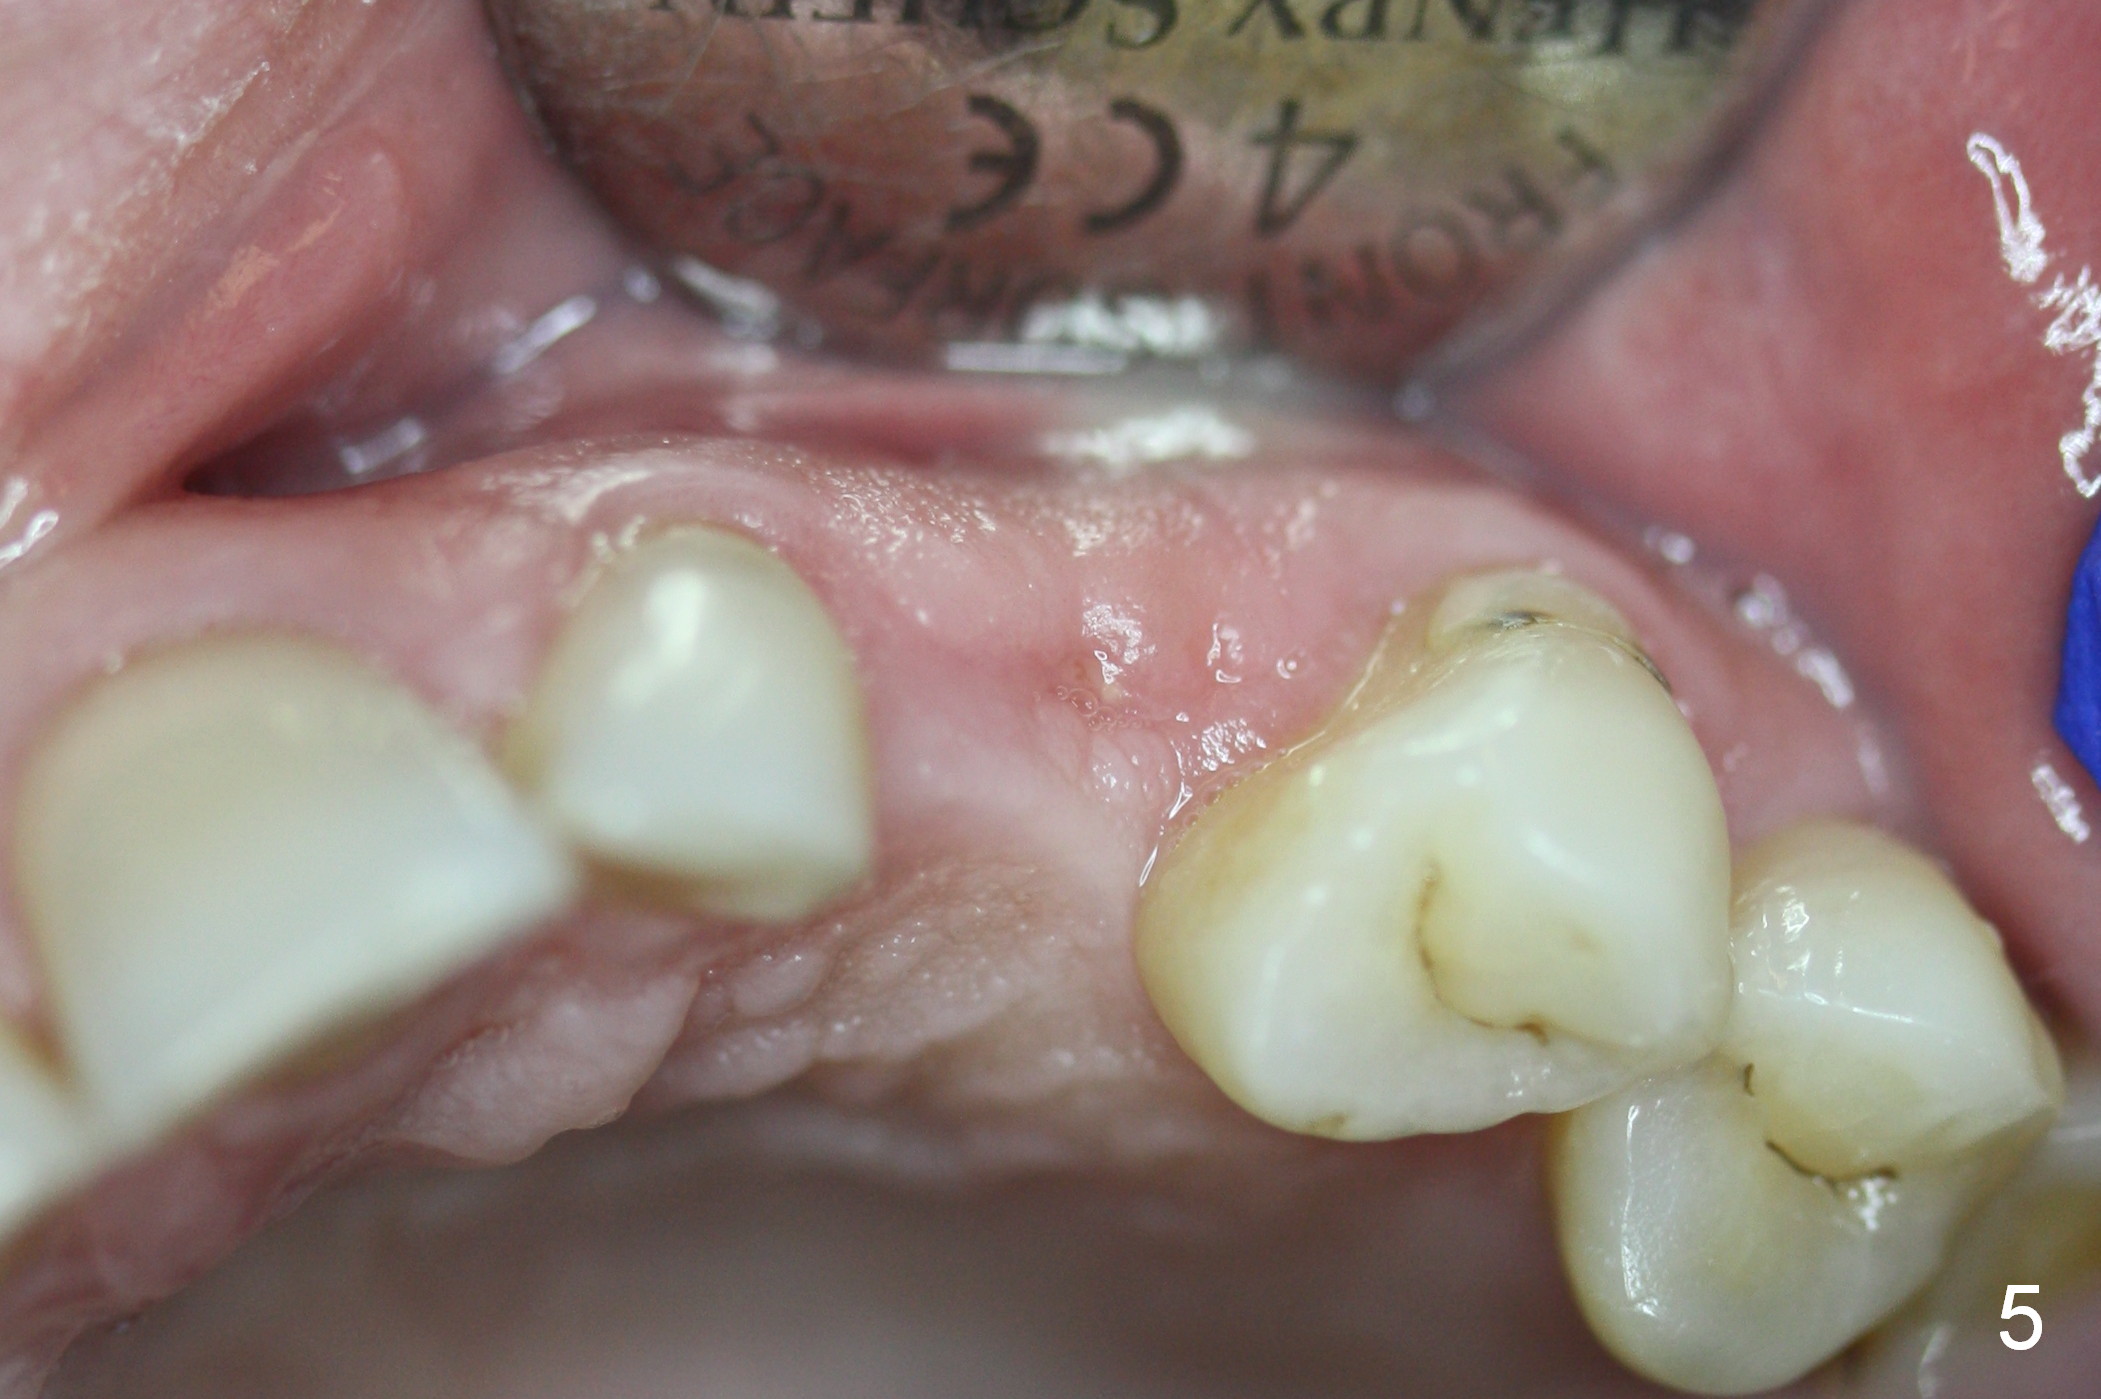

One month post-implantation at the site of the upper left deciduous canine, the patient returns for follow-up with chief complaint "The crown is a little loose. A bubble is becoming smaller". Exam shows an abscess (Fig.1 <) above the provisional (#11). The provisional is loose with mild tenderness. A pull on the provisional leads to dislodgement of the abutment and implant. Raising the buccal flap reveals perforation of the buccal plate with granulation tissue (Fig.2). After debridement (Fig.3), allograft and Osteogen is placed in the defect, followed by Osteotape (Fig.4 *) and suture. This complication can be prevented by CT information. A deciduous tooth socket is small. The immediate implant should be not too large, leaving 2 mm buccal gap. Three months 20 days post graft, the ridge looks not so atrophic (Fig.5). There is no sign of bone resorption (Fig.6). The patient will return for implant placement for the second time soon. Measure the bone width with bone caliper after local anesthesia. Fully expose the alveolus. Start osteotomy as palatal as possible. Repeatedly check osteotomy position and trajectory. Use surgical stent. The implant will not be too long or too wide. Is the ridge as wide as clinically shown?